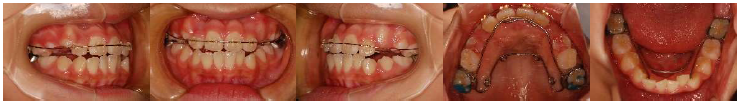

治療開始6か月後、前歯の咬み合わせが良くなりました。まだ治療途中ですが、顎も広がりスペースが出来てきました。このような流れで咬み合わせと歯並びを治していきます。全ての反対咬合を同じ方法で治せるわけではありませんが、早期に介入することで成長の方向を良い方へ向かわせられることができます。反対咬合に気づいたら、まずは受診を!